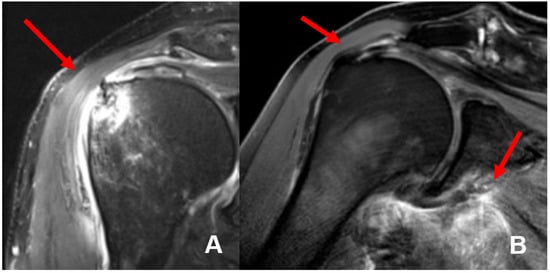

The mean interval between trauma and MR imaging was 6.9 days (0–14 days). In 8 of 21 patients (38%), we found 11 concomitant intra-articular glenohumeral lesions. In three patients (14.3%), two lesions occurred at the same time. In total, three partial bursa sided tears of the supraspinatus tendon (14.3%) and five (23.8%) partial articular sided supraspinatus tendon tears were found. Two patients (9.5%) had a partial tear of the subscapularis tendon Fox and Romeo I (9.5%), whereas only one (4.8%) complete transmural supraspinatus tendon tear was detected (see Figure 4). In none of the detected concomitant intra-articular glenohumeral injuries, a fatty degeneration or/and atrophy of the rotator cuff musculature was found. Moreover, indirect signs of acute rotator cuff injury were found in terms of the 1st bone bruise of the lesser and respectively the greater tuberosity and 2nd joint effusion in terms of acute hematoma; so that the injuries were considered as an acute traumatic tear (see Figure 5).

Figure 4. Concomitant intra-articular injuries detected through preoperative magnetic resonance imaging (MRI) and of affected shoulder.